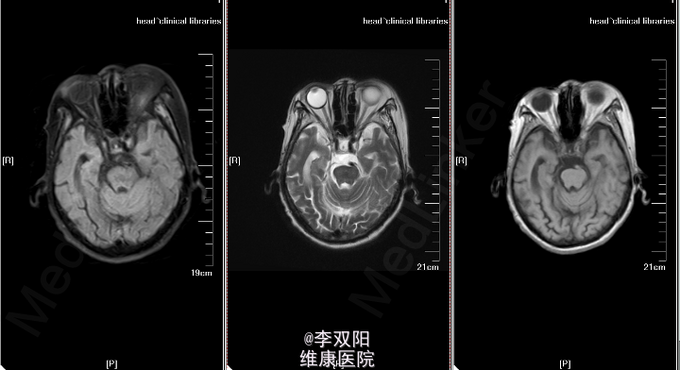

查体:体温36.2℃,脉搏58次/分,呼吸20次/分,血压150/90mmHg。轮椅推入病房,查体合作。皮肤巩膜无黄染,双肺呼吸音清,未闻及罗音,心率58次/分,律齐,无病理性杂音,腹部平软,肝脾肋下未触及。 神经系统专科查体:神志模糊,失语,双瞳孔同大同圆,直径3.0mm,对光反射灵敏,眼球各方向可活动,无眼震及复视,鼻唇沟对称,咽反射(+),伸舌不合作,四肢肌力2级,肌张力增高,肱二头肌、肱三头肌肌腱及膝反射、跟腱反射均对称,感觉及共济运动检查不合作,Hoffmann征L(-),R(-),病理征:Babinski征L(+),R(+),颈无抵抗,Kernig征(-)。 辅助检查:头颅CT扫描示:双侧基底节区及丘脑区斑片状低密度影,双侧脑室周围及双侧半卵圆中心见片状密度减低区,边缘模糊不清。双侧脑室扩张,脑沟裂增宽,中线结构居中。 头MRI+DWI:双侧基底节区及丘脑区斑片状低密度影,双侧脑室周围及双侧半卵圆中心见片状密度减低区,边缘模糊不清。双侧脑室扩张,脑沟裂增宽,中线结构居中。